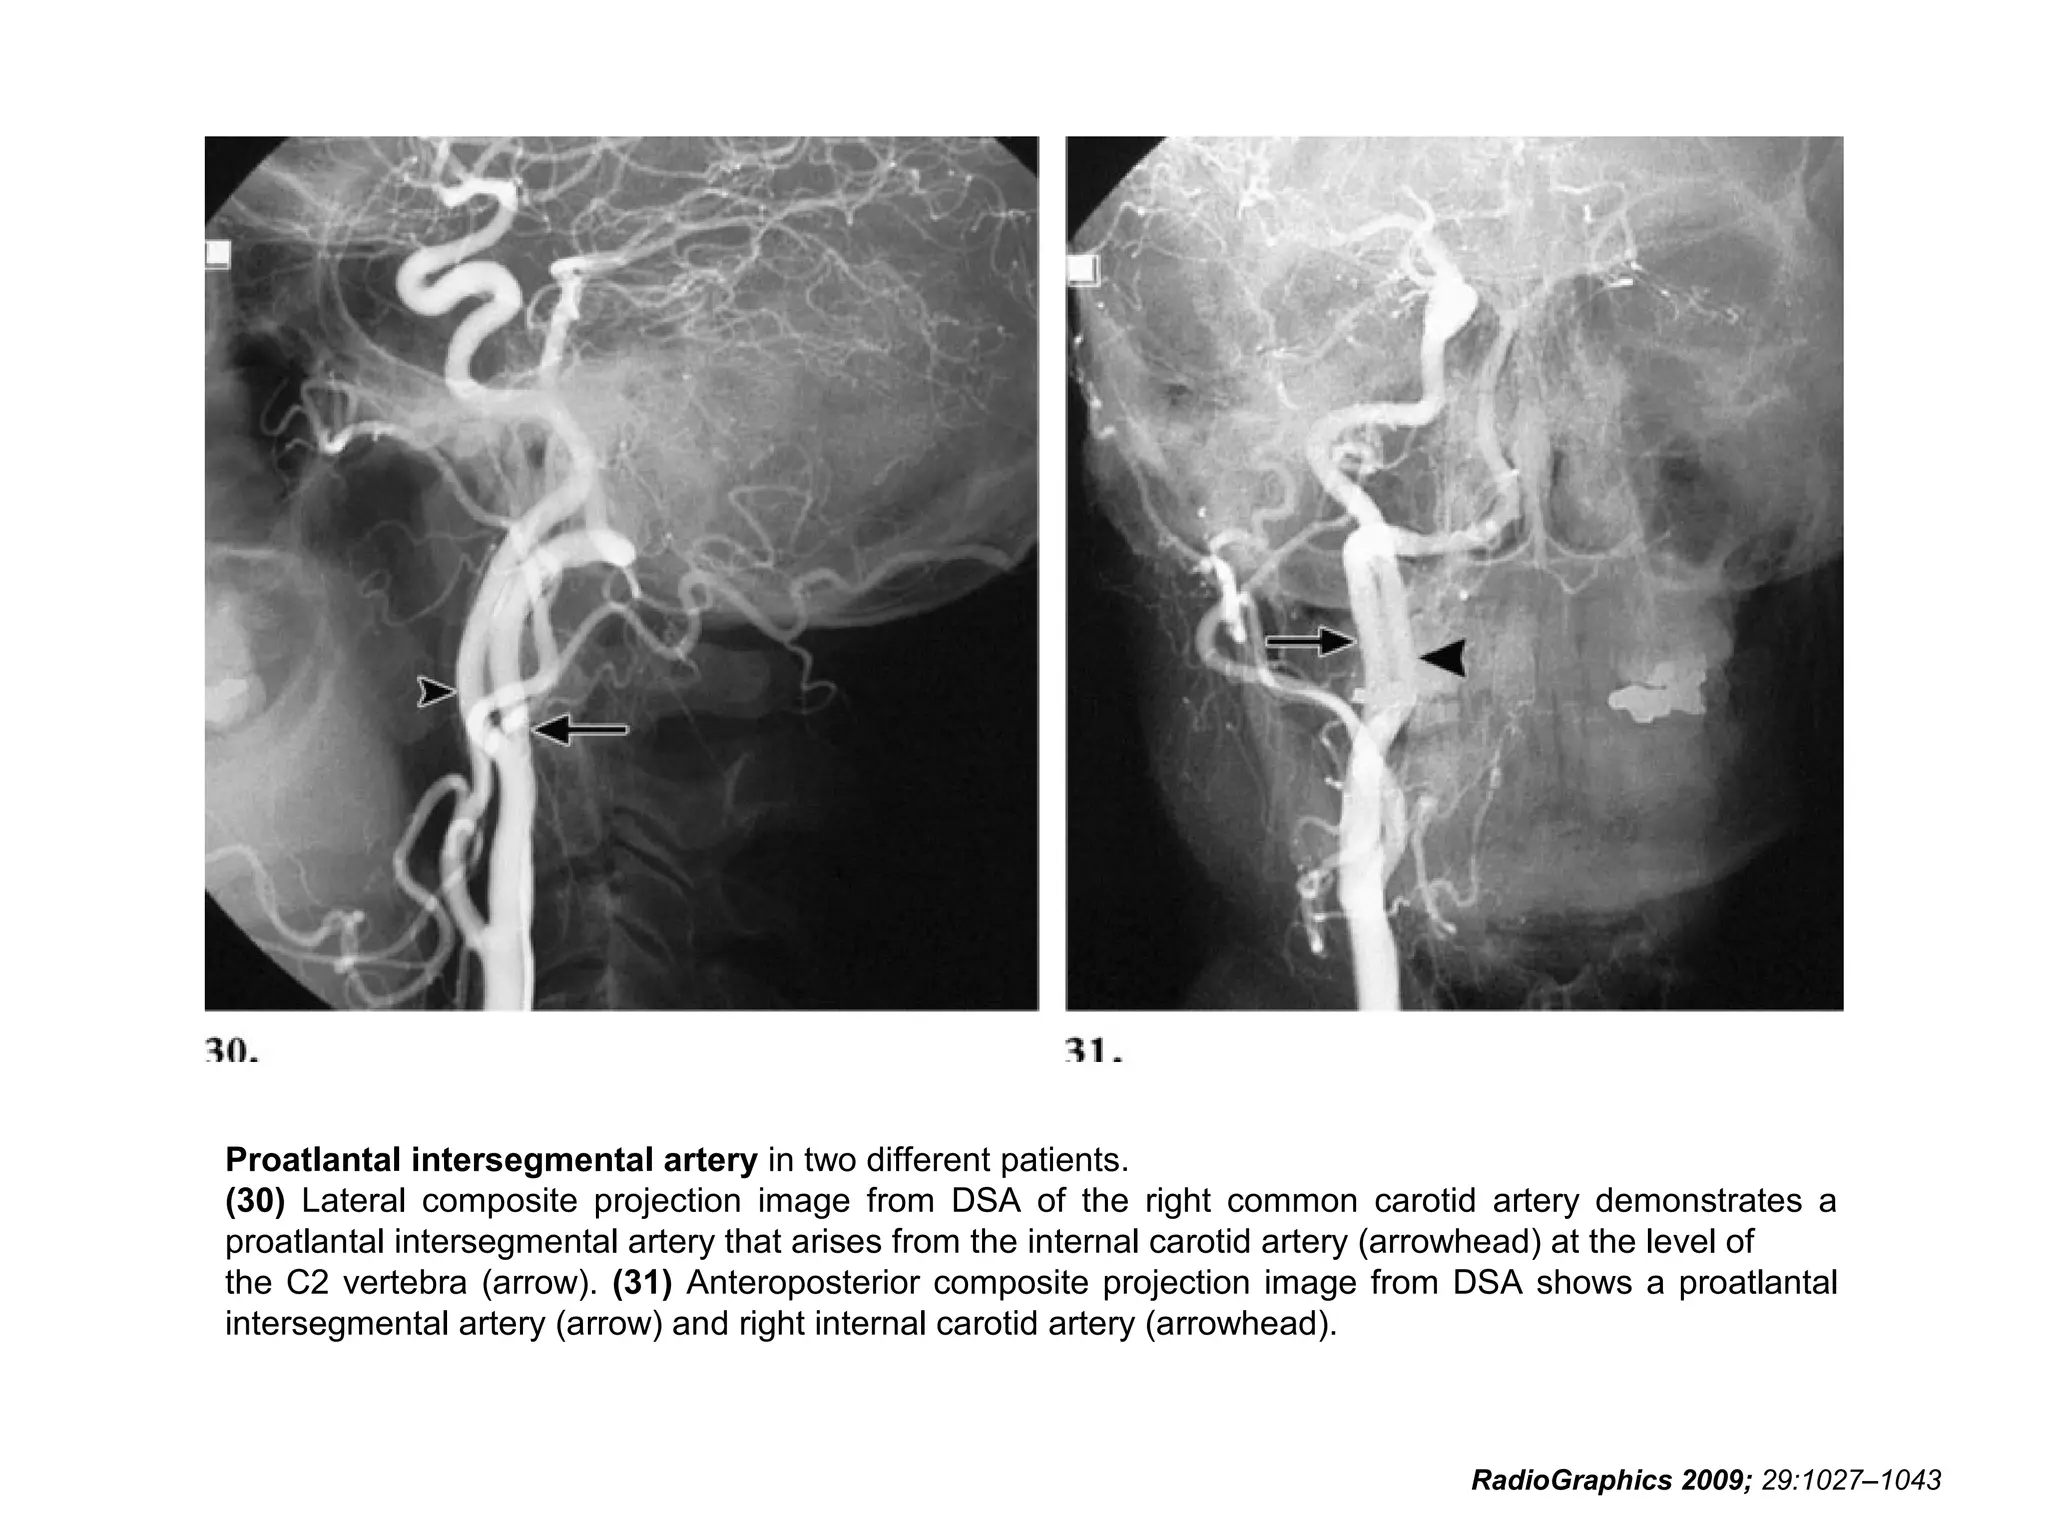

Proatlantal Intersegmental Artery

• The proatlantal intersegmental artery originates from the

common carotid artery bifurcation, external carotid

artery, or internal carotid artery at the levels of the C2

through C4 vertebral bodies; joins the horizontal part of

the vertebral artery in the suboccipital region; and

traverses the foramen magnum.

• Aplasia or hypoplasia of one or both

vertebral arteries proximal to the

anastomosis may be identified in 50% of

cases.

• In addition, cerebrovascular abnormalities

were found in 59% of patients with a

proatlantal intersegmental artery.

• Such abnormalities included intracranial

aneurysm in 10% of patients.

Proatlantal intersegmental artery in two different patients.

(30) Lateral composite projection image from DSA of the right common carotid artery demonstrates a

proatlantal intersegmental artery that arises from the internal carotid artery (arrowhead) at the level of

the C2 vertebra (arrow). (31) Anteroposterior composite projection image from DSA shows a proatlantal

intersegmental artery (arrow) and right internal carotid artery (arrowhead).